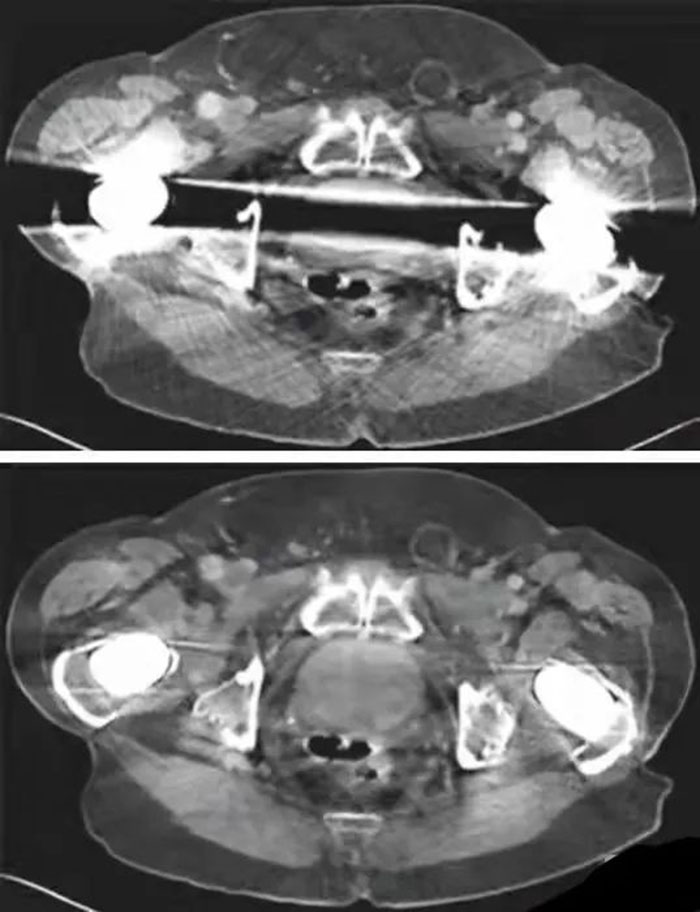

西门子SOMATOM Drive双源CT具有超高的扫描速度及时间分辨率,在全新Turbo Flash技术的支持下,完成全身动脉检查仅需3秒,冠状动脉扫描更是无需严格限制心率。对于胸部肺动脉扫描检查,扫描时间不到1秒,可以得到清晰的肺动脉图像,避免肺静脉干扰。完成2米范围全身动脉扫描仅需3秒,即可得到清晰图像。全新0兆球管性能优异,可持续行大范围扫描,轻松应对双下肢动脉CTA检查。

SOMATOM Drive CT行血管CTA检查(如冠状动脉、头颈部血管、全主动脉、下肢动脉CTA等检查),对比剂使用量仅为之前CTA检查的一半,极大减少了对比剂对身体的负荷。

最新ADMIRE基于原始数据域的迭代重建技术,不仅可以大幅降低图像噪声,降低伪影影响,还可以降低扫描辐射剂量,在骨科检查方面具有巨大优势。